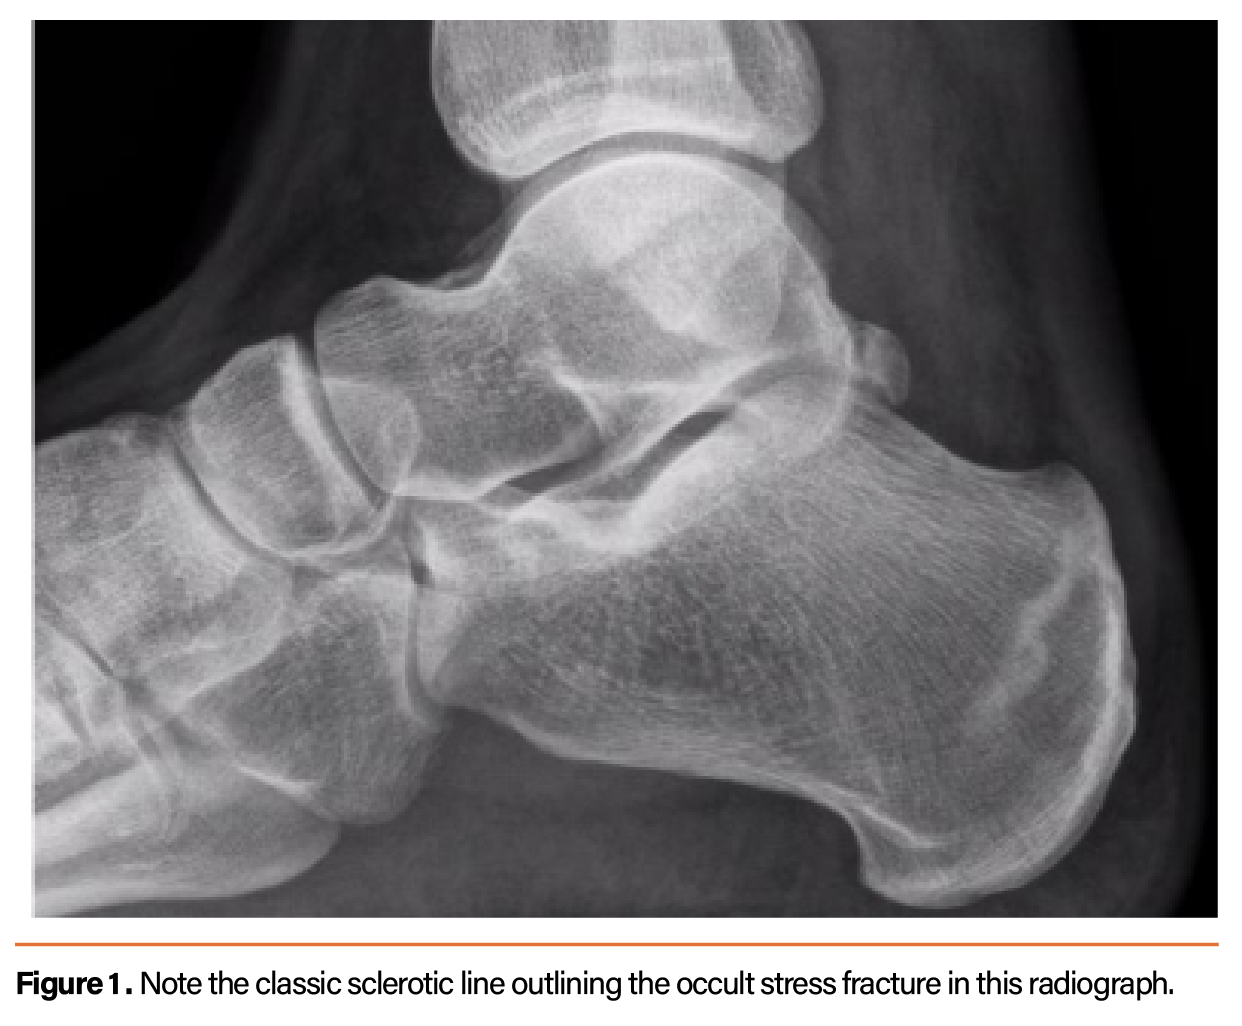

Understand the role of a heel spur X-ray in diagnosing chronic foot pain. Learn how imaging identifies bony calcium deposits, assesses plantar fasciitis, and helps doctors determine the most effective treatment plan for your heel discomfort. Get expert insights into diagnostic procedures and recovery options for lasting relief from persistent heel pain today.